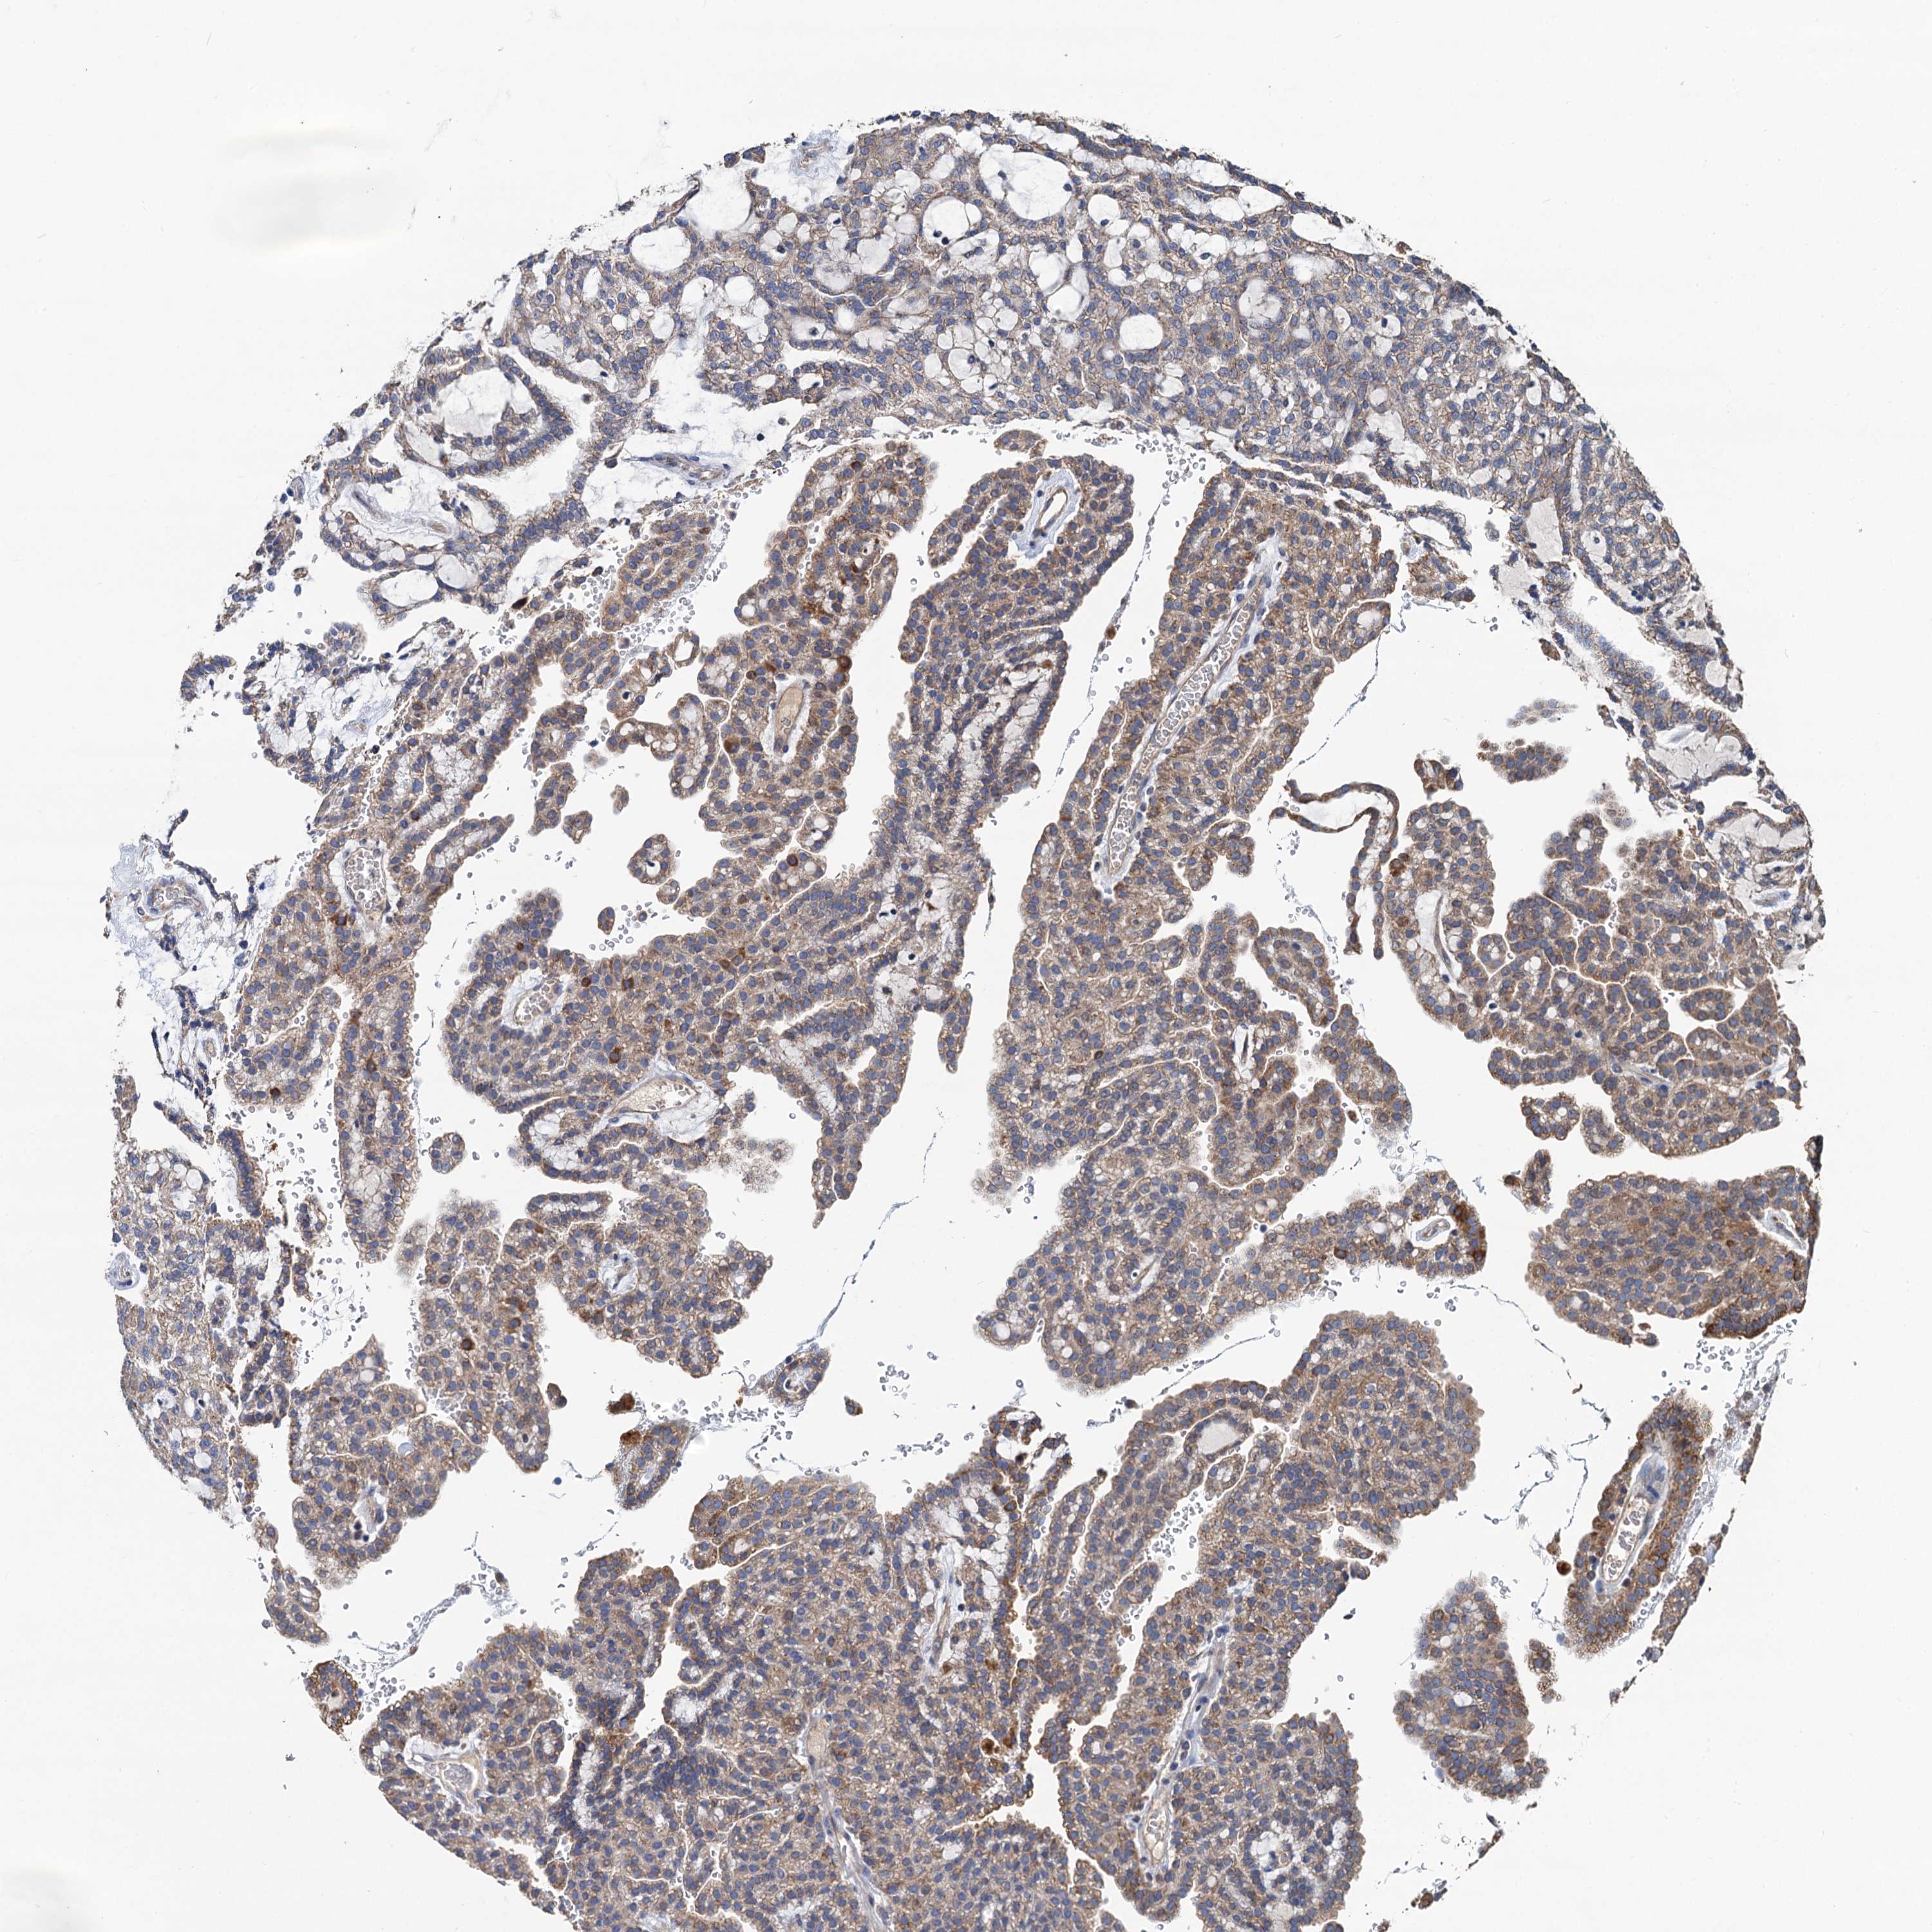

KIDNEY RENAL CLEAR CELL CARCINOMA (VALIDATION) - Interactive survival scatter ploti

The Survival Scatter plot shows the clinical status (i.e. dead or alive) for all individuals in the patient cohort, based on the same data that underlies the corresponding Kaplan-Meier plots. Patients that are alive at last time for follow-up are shown in blue and patients who have died during the study are shown in red.

The x-axis shows the expression levels (FPKM) of the investigated gene in the tumor tissue at the time of diagnosis. The y-axis shows the follow-up time after diagnosis (years). Both axes are complimented with kernel density curves demonstrating the data density over the axes. The top density plot shows the expression levels (FPKM) distribution among dead (red) and alive patients (blue). The right density plot shows the data density of the survived years of dead patients with high and low expression levels respectively, stratified using the cutoff indicated by the vertical dashed line through the Survival Scatter plot. This cutoff is automatically defined based on the FPKM cutoff that minimizes the p-score. The cutoff can be changed by dragging the vertical line or by entering a cutoff value in the square labeled "Current cut-off".

Under the Survival Scatter plot the p-score landscape (black curve; left axis) is shown together with dead median separation (red curve; right axis). Dead median separation is the difference in median mRNA expression between patients who have died with high and low expression, respectively. It is calculated as follows: median FPKM expression of dead patients with high expression - median FPKM expression of dead patients with low expression. This is intended to aid the user in visually exploring custom cutoffs and the associated p-scores and dead median separation.

Individual patient data is displayed and can be filtered by clicking on one or more of the category buttons on the top of the page. Categories describing expression level and patient information include: high, low, alive, dead, female, male and tumor stages. The scale of the x-axis can be toggled between linear and log-scale by clicking on the "x log" button. Mouse-over function shows TCGA ID, patient information and mRNA expression (FPKM) for each patient.

& Survival analysisi

Kaplan-Meier plots summarize results from analysis of correlation between mRNA expression level and patient survival. Patients were divided based on level of expression into one of the two groups "low" (under cut off) or "high" (over cut off). X-axis shows time for survival (years) and y-axis shows the probability of survival, where 1.0 corresponds to 100 percent.

DGLUCY is not prognostic in Kidney Renal Clear Cell Carcinoma (validation)

Best expression cut offi

Based on the FPKM value of each gene, patients were classified into two groups and association between prognosis (survival) and gene expression (FPKM) was examined. The best expression cut-off refers the FPKM value that yields maximal difference with regard to survival between the two groups at the lowest log-rank P-value. Best expression cut-off was selected based on survival analysis .

When clicking on this number, the vertical dashed line indicating cut-off, the interactive survival plot, and the Kaplan-Meier curve will be adjusted to show results based on the best expression cut-off.

: 26.03

P scorei

Log-rank P value for Kaplan-Meier plot showing results from analysis of correlation between mRNA expression level and patient survival.

N/A

TCGA RNA samplesi

RNA-seq data is reported as average FPKM (number Fragments Per Kilobase of exon per Million reads), generated by the The Cancer Genome Atlas (TCGA) .

Normal distribution across the dataset is visualized with box plots, shown as median and 25th and 75th percentiles. Points are displayed as outliers if they are above or below 1.5 times the interquartile range. FPKM values of the individual samples are presented next to the box plot.

Average pTPM 30.0

Number of samples 100